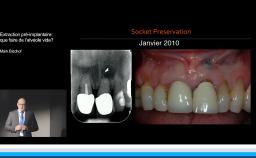

A partir de la description des facteurs de risque esthétique du bloc incisivo-canin maxillaire, de la présence d’os et de gencive autour des implants, le conférencier présente une succession de cas cliniques décrivant ses procédures chirurgicales et prothétiques.

- de déterminer le bon timing de chirurgie implantaire post extractionnelle

- de réfléchir sur la préservation à moyen-long terme de l’os autour des implants